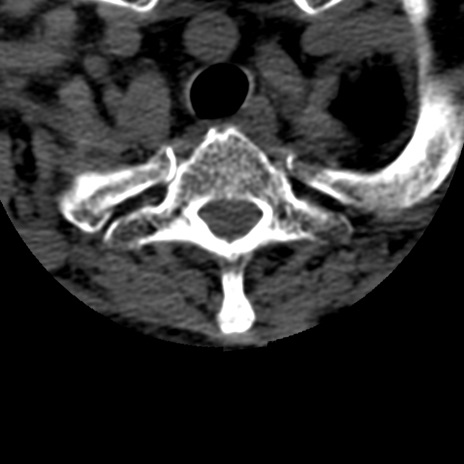

症例50 頚椎CT(横断像)

頚椎CT